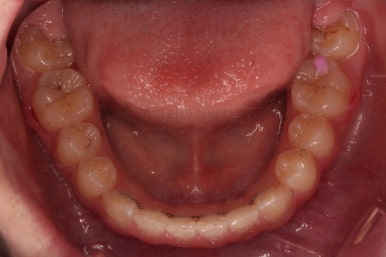

마무리를 해줍니다.

앞니 각도가 매우 좋아졌고요.(옥니 개선) 위아래 앞니가 덮는 정도도 개선이 되었어요.(과개교합, 딥바이트)

엉성했던 어금니 맞물림도 매우 좋아졌어요.(앵글씨 2급 부정교합 개선)